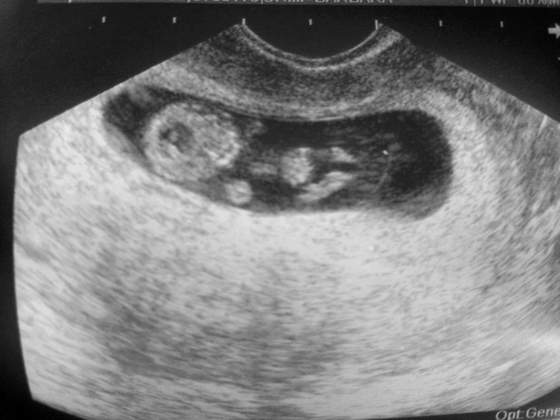

Boskie malenstwo!Tak jak obiecalam dziewczyny. Kolejne fotki mojej modelki/ modela ♡ Z dzisiaj tj. 9+2. Moja nowa milosc ma 27,05mm :-):-):-)

Zobacz załącznik 564201Zobacz załącznik 564200